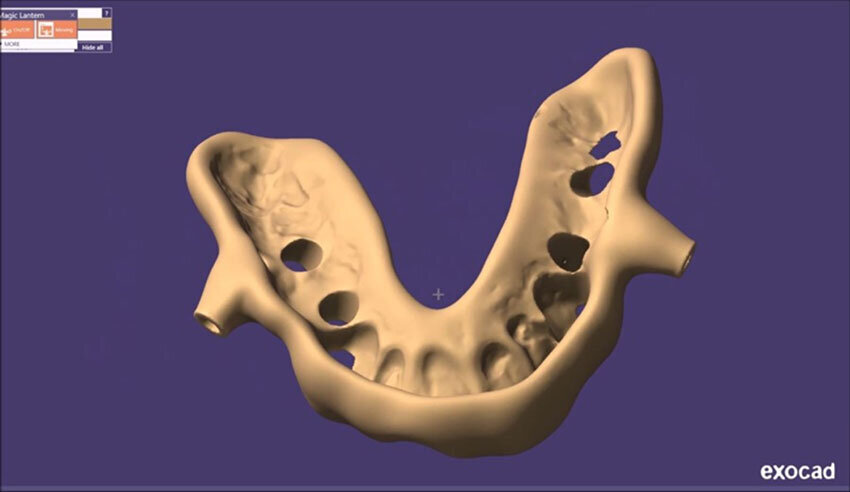

Figg. 21-25_Progettazione Cad con exocad.